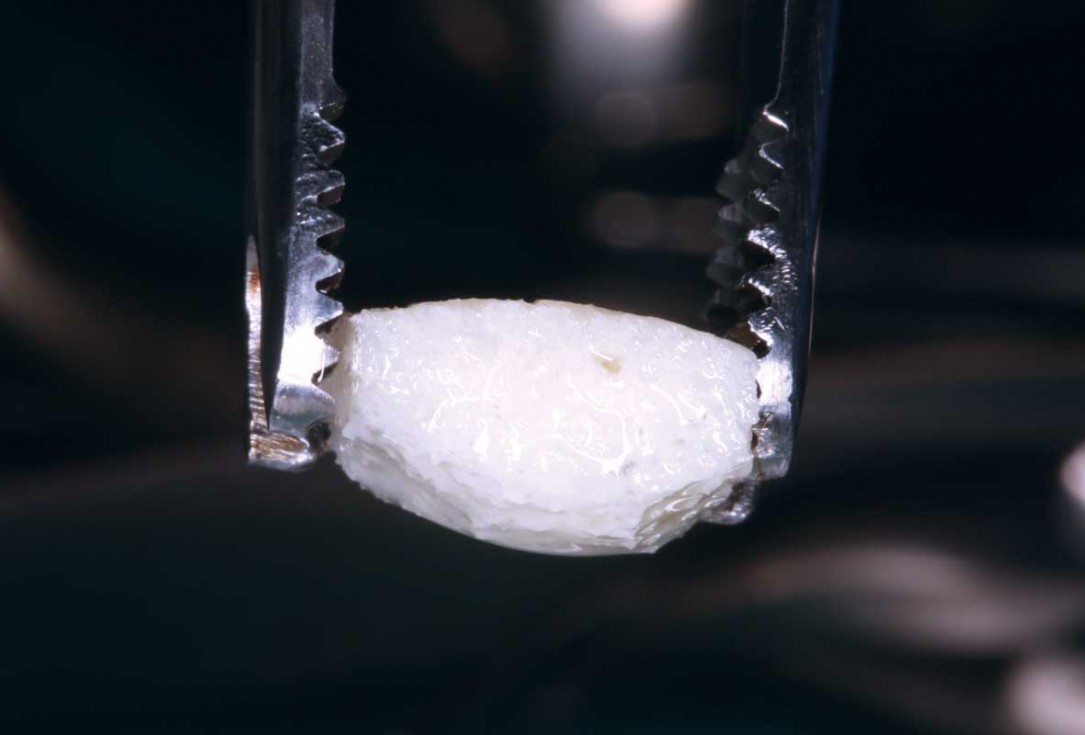

7/35 - Shaping and preparing the uni-cortical maxgraft® block using straight hand-piece under copious irrigation to fit the surgical field and to ensure good adaptationBlock grafting in the aesthetic zone with maxgraft®, Jason® membrane and cerabone® - Dres. H. Maghaireh and V. Ivancheva

8/35 - Shaping and preparing the uni-cortical maxgraft® block using straight hand-piece under copious irrigation to fit the surgical field and to ensure good adaptationBlock grafting in the aesthetic zone with maxgraft®, Jason® membrane and cerabone® - Dres. H. Maghaireh and V. Ivancheva